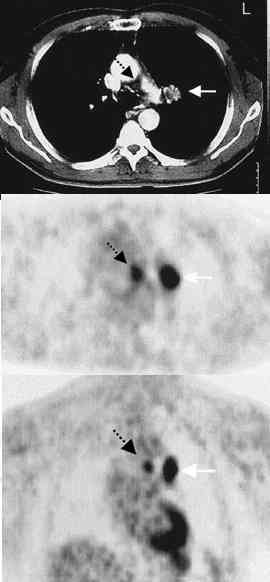

We prospectively compared the ability of a standard approach to staging (computed

tomography [CT], ultrasonography, bone scanning, and, when indicated, needle biopsies) and

one involving PET to detect metastases in mediastinal lymph nodes and at distant sites in

102 patients with resectable non-small-cell lung cancer. The presence of mediastinal

metastatic disease was confirmed histopathologically. Distant metastases that were

detected by PET were further evaluated by standard imaging tests and biopsies. Patients

were followed postoperatively for six months by standard methods to detect occult

Results. The sensitivity and specificity of PET for

the detection of mediastinal metastases were 91 percent and 86 percent, respectively.

The corresponding values for CT were 75 percent and 66 percent. When the results of

PET and CT were adjusted for each other, only PET results were positively correlated with

the histopathological findings in mediastinal lymph nodes. Conclusions. PET